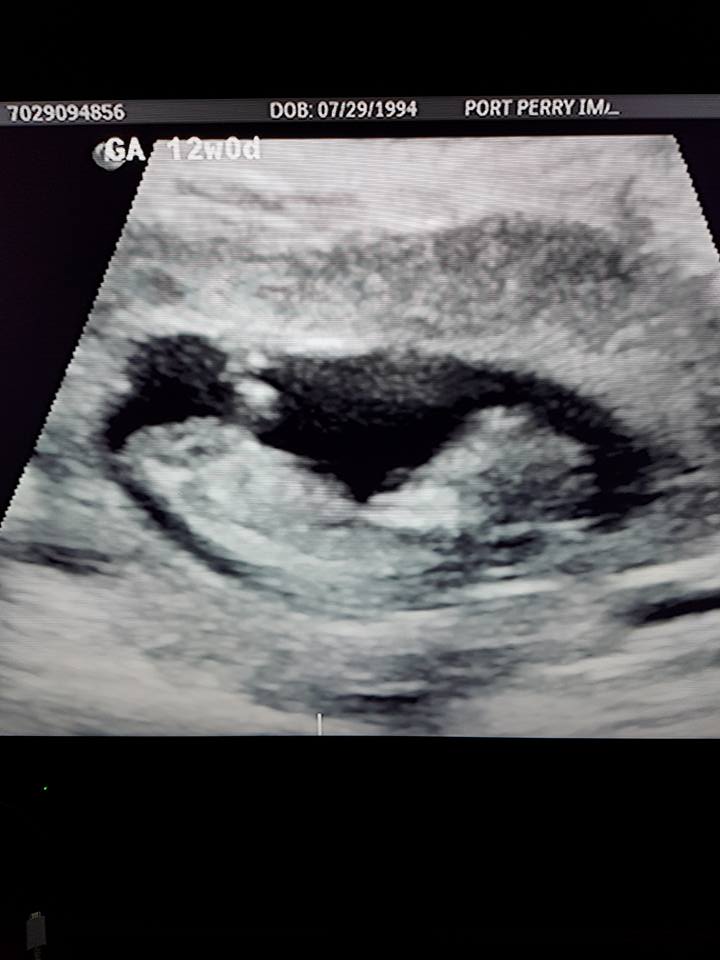

Hi! Just wondering if there is a nub in these photos, and if so, if you would guess it's a boy or girl? 12+0 weeks. Thank you!Attachment 38349Attachment 38350Attachment 38351Attachment 38352Attachment 38353